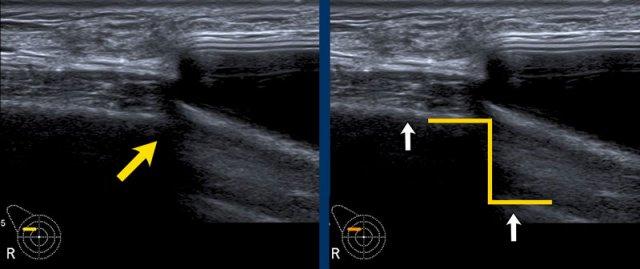

Dấu hiệu Oreo ngược

Vỏ bọc của túi độn có thể được nhìn thấy như một chiếc bánh Oreo lật ngược. Đường trắng đầu tiên là mặt tiếp xúc bên ngoài của vỏ bọc và đường trắng thứ hai là mặt tiếp xúc bên trong giữa vỏ bọc và gel Silicone (mũi tên vàng).

Giữa lớp ngoài của vỏ bọc và bao xơ xung quanh tồn tại một khoang ảo có thể được lấp đầy và giãn rộng.

Bao xơ được nhìn thấy tách biệt khỏi vỏ bọc như một đường trắng riêng biệt nằm phía trước vỏ bọc (mũi tên trắng).

Vỏ bọc và bao xơ cùng nhau được gọi là phức hợp vỏ bọc-bao xơ.